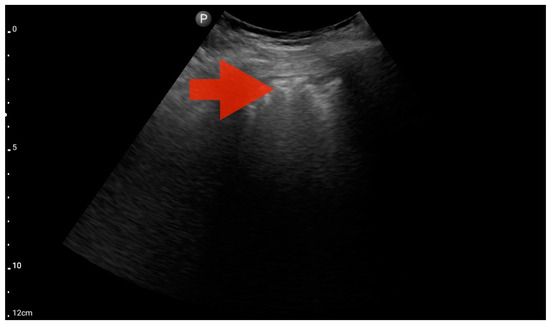

Figure 15.

Inferior vena cava (IVC) dilation. Sector probe; the red arrow marks the inferior vena cava; the width is not dependent on the phase of the patient’s breath and shows significant dilatation (source: author’s material—DK).